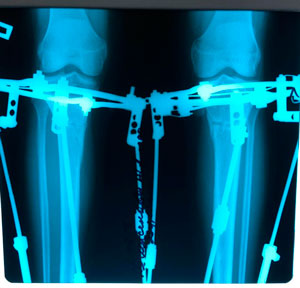

рентген в 60 дней.

рентген перед снятием аппаратов